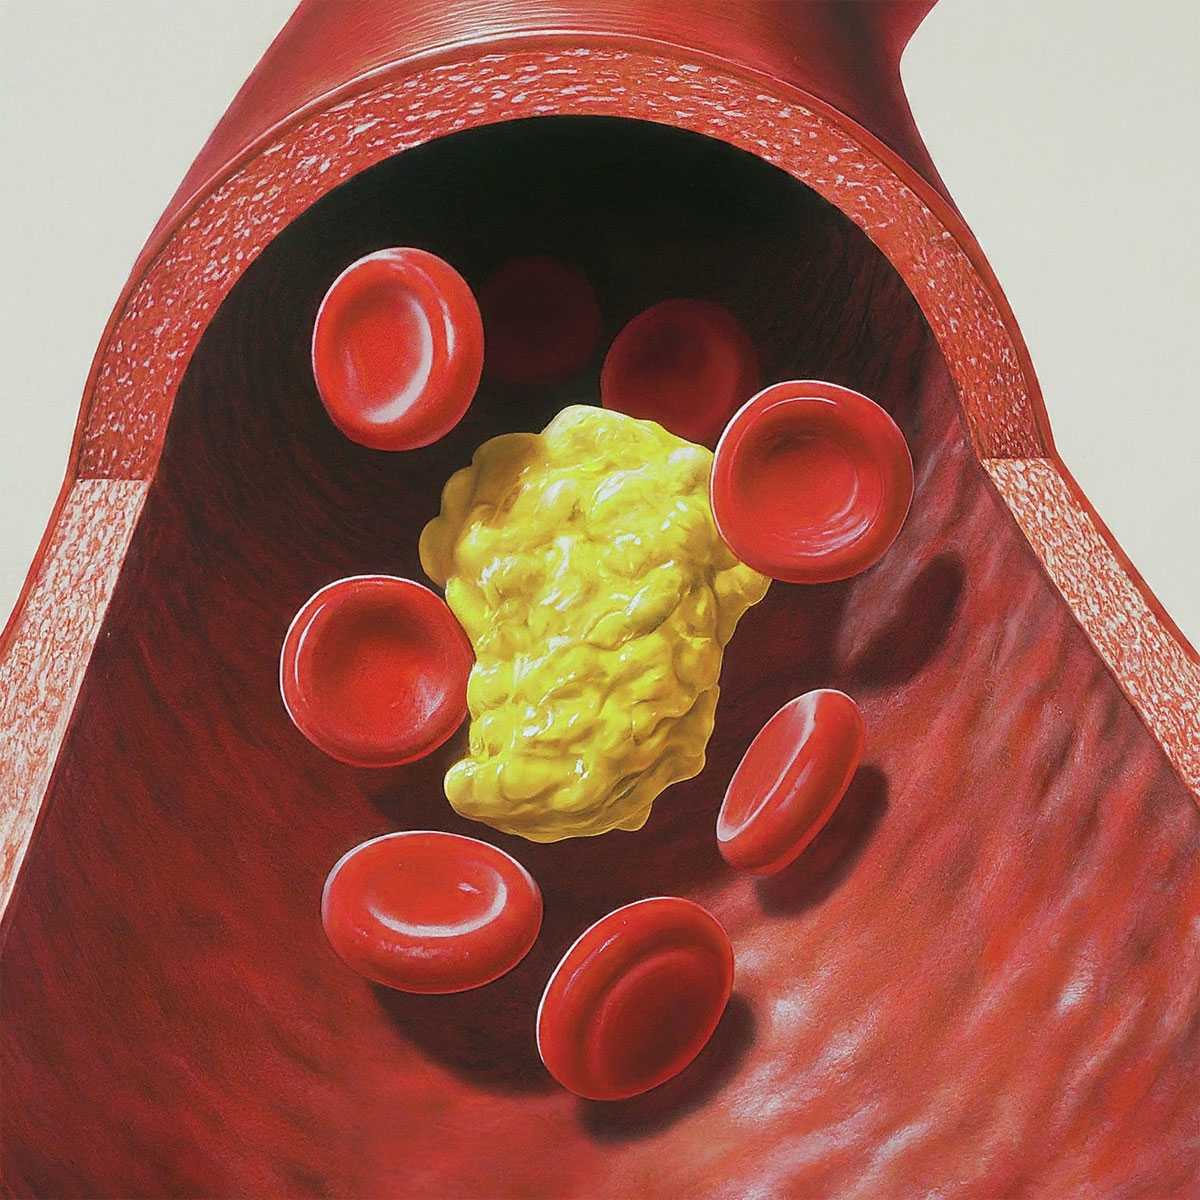

Холестерин в организме: влияние и функции (схемы и диаграммы)